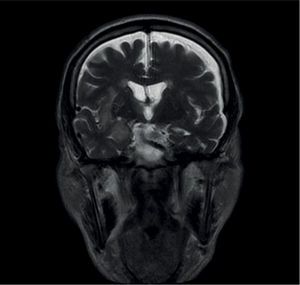

Los síndromes paraneoplásicos son las manifestaciones clínicas de un tumor que no están relacionadas con la invasión directa del tumor primario o de sus metástasis. Se excluyen asimismo las complicaciones cerebrovasculares, infecciosas, metabólicas nutricionales o tóxicas asociadas a las neoplasias y también las derivadas del tratamiento (quirúrgico, radioterapia, quimioterapia o terapias biológicas). Comprenden un grupo heterogéneo de síndromes que pueden afectar a cualquier parte del sistema nervioso central (SNC) o periférico (SNP), unión neuromuscular y músculo, y en ocasiones en el mismo paciente en múltiples áreas. Son poco frecuentes, con una incidencia general en pacientes con cáncer inferior al 1%. La incidencia varía con el tipo de tumor, siendo los más implicados el cáncer de pulmón de células pequeñas (CPCP) con un 3% de incidencia. La presencia de anticuerpos onconeuronales apoya el diagnóstico en un síndrome clínico compatible; sin embargo, solo están presentes en aproximadamente un 50% de los casos, por lo que su ausencia no descarta el diagnóstico. Como ya se ha mencionado anteriormente, el síndrome paraneoplásico se puede producir en pacientes con una neoplasia ya diagnosticada, pero en muchos casos esta no es aparente, por lo que es preciso ante la presencia del síndrome la búsqueda de la neoplasia oculta. Si es posible se debe iniciar el tratamiento lo antes posible, pues los síndromes paraneoplásicos evolucionan en unas semanas, pudiendo producir un daño irreversible e incluso la muerte del paciente.

Paraneoplastic syndromes are clinical manifestations of a tumor that are not related to the direct invasion of the primary tumor or its metastases. Therefore, cerebrovascular, infectious, nutritional metabolic, or toxic complications associated with neoplasms and also treatment-derived complications (surgery, radiotherapy, chemotherapy, or biologic therapies) are excluded. They comprise a heterogeneous group of syndromes that can affect any part of the central nervous system (CNS) or peripheral nervous system (PNS), neuromuscular junction, and muscle and occasionally affect multiple areas in the same patient. They are uncommon, with a general incidence in patients with cancer of less than 1%. Incidence varies according to the type of tumor, with small cell lung cancer (SCLC) being the most commonly involved, with an incidence of 3%. The presence of onconeural antibodies supports the diagnosis of a compatible clinical syndrome. However, they are only present in approximately 50% of cases and therefore its absence does not rule out a diagnosis. As previously stated, paraneoplastic syndrome can occur in patients with an already-diagnosed neoplasm, but it is not apparent in many cases. Therefore, the search for the occult neoplasm is necessary when the syndrome is present. If possible, treatment must be started as soon as possible, given that paraneoplastic syndromes progress in weeks and can cause irreversible damage or even the patient's death.